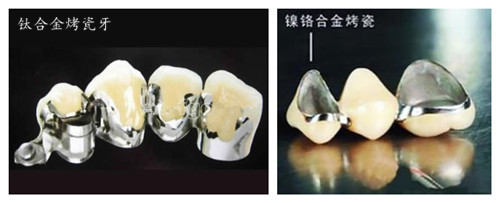

非贵金属烤瓷牙虽然价格低廉,但是与组织的相容性差,刺激性较大,可发生过敏现象及变色,因此不建议患者选用这种材料的烤瓷牙。

半贵金属烤瓷牙的代表是钛合金,主要成分是钛或者钯-银,钛合金烤瓷牙的价格介于非贵金属和贵金属之间,其生物相容性优于非贵金属,也比较耐久,可以避免牙龈出血及牙龈黑线的出现,而且经济、实用,适合大多数牙齿的修复,尤其适合后牙固定桥等固定修复。>>>更多详情,在线咨询<<<

贵金属烤瓷牙的代表就是金合金烤瓷牙。黄金在我国很早就用作补牙的材料了,它是较理想的修复材料之一,拥有钛合金的优点,且强度更高,无刺激,而且金与瓷的结合很牢固,与组织的相容性更好,在瓷牙与牙龈接触的地方不会发黑。